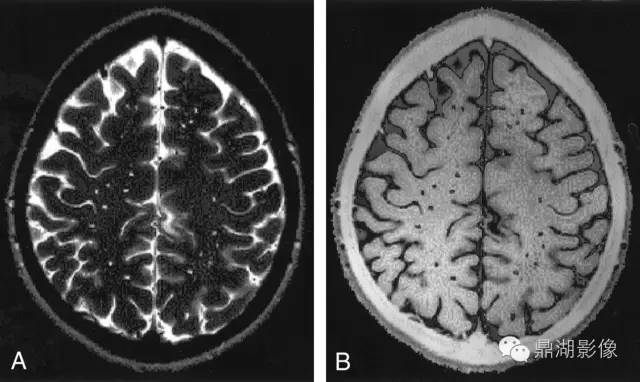

以上两图对照阅读

4.2 MRI

MRI是目前检测CSVD最重要的工具。常规检查序列包括:T1加权成像(T1WI)、T2加权成像(T2WI)、弥散加权成像(DWI)、FLAIR、梯度回波序列(GRE)、磁敏感加权成像(SWI),此外还有弥散张量成像(DTI)、静息态功能磁共振等。而MRI上可观察到的CSVD影像学改变主要有如下几种。